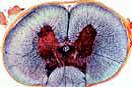

721c Rückenmark der Katze, quer. Graue und weiße Substanz, große motorische Nervenzellen, Nervenfasern

Artikel-Nr.: LI700

Schulserie C, 50 Mikroskopische Präparate

791.00 CHF exkl. MwSt.

Lieder - made in Germany